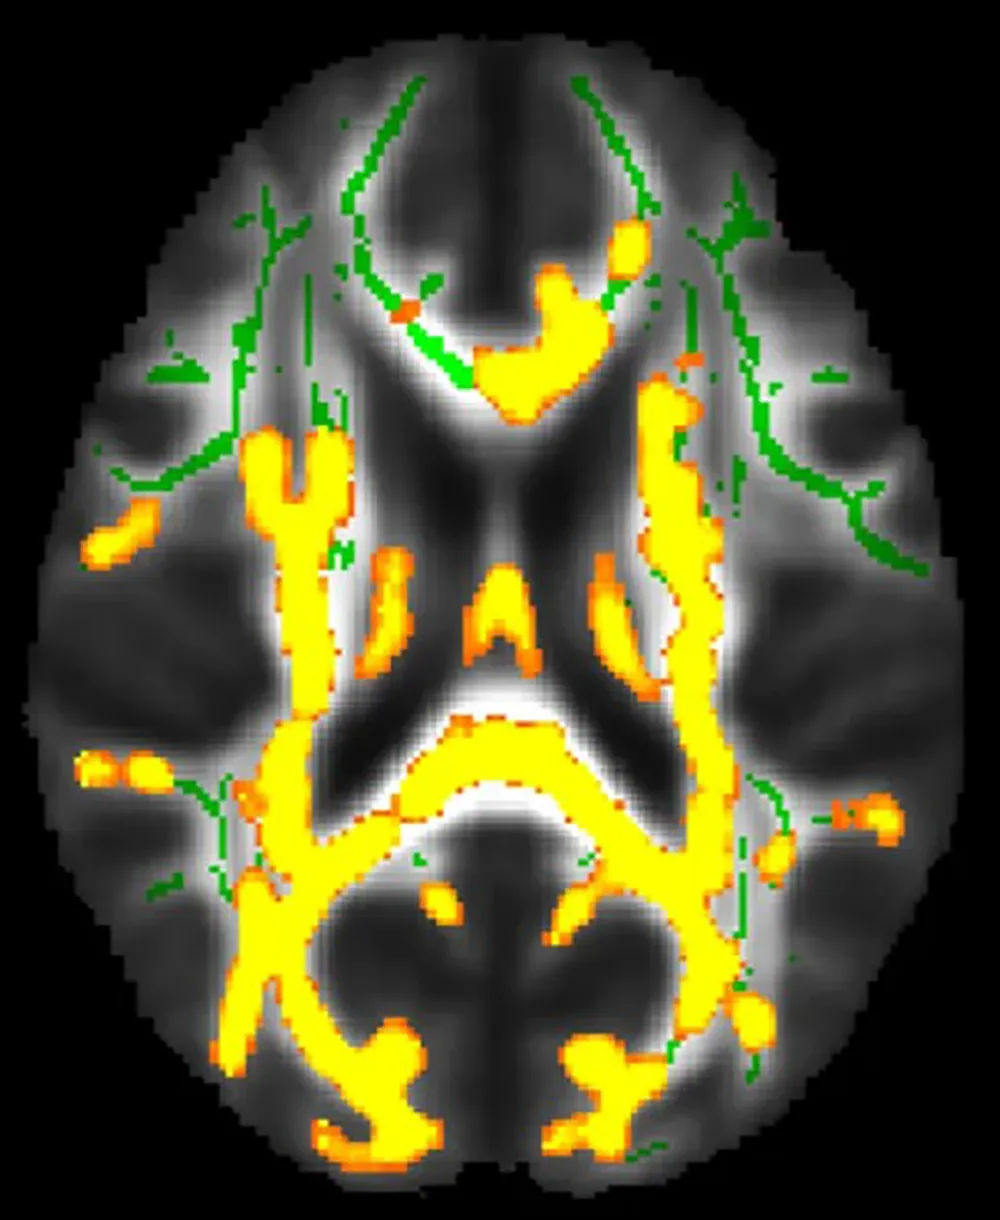

| Kết quả quét não cho thấy tình trạng viêm thần kinh gia tăng với lượng mỡ nội tạng cao hơn. Ảnh: CNN |

Theo đó, tỷ lệ mỡ nội tạng và mỡ dưới da có liên quan đến sự hấp thu amyloid cao hơn ở vỏ não trước, khu vực bị ảnh hưởng sớm bởi bệnh Alzheimer. Các nhà nghiên cứu cũng phát hiện ra rằng, lượng mỡ nội tạng cao hơn có liên quan đến việc tăng gánh nặng viêm não - một trong những cơ chế chính góp phần gây ra bệnh Alzheimer.